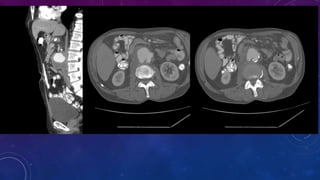

PRE TRANSPLANT

EVALUATION

FAILED BILATERAL RENAL TRANSPLANTS

CALCIFICATION

• #62 Failed kidney transplant Seminal vesicle / vas deferens calcification